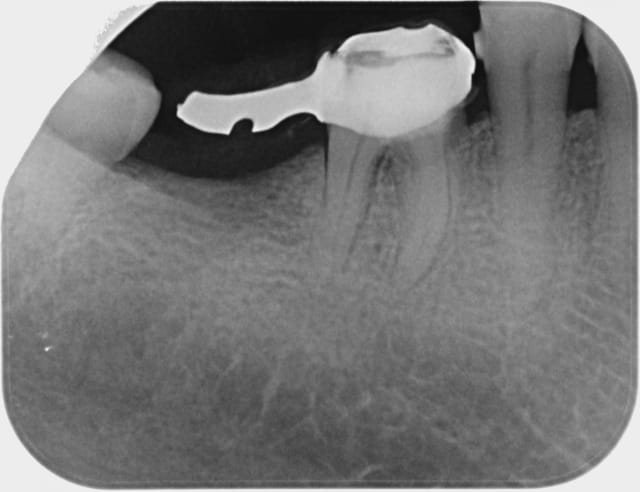

je vois cette patient de 62 ans pour la premiére fois en novembre 2010, elle me demande une rehabilitation des secteurs édentés, sont absentes 14, 15, 47,et 36 toutes les autres dents sont ultra saines, pas de tartre, un excellent controle de plaque, seul "hic" la patient à une valvulopathie qui la classe dans les patients à risque A...

Puis le temps passe, elle reviens en urgence la semaine derniére pour une pulpite et saignement des gencicves,

et là je découvre ça...(cf radio) fait au bled il y a un mois, pour une fortune là bas en depis de tout ce qu'on s'est acharné à lui expliquer. dommage.